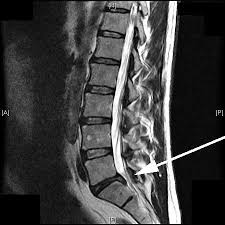

Verengung Des Spinalkanals Der Lendenwirbelsaule Schulthess Klinik

Verengung Des Spinalkanals Der Lendenwirbelsaule Schulthess Klinik from www.schulthess-klinik.ch